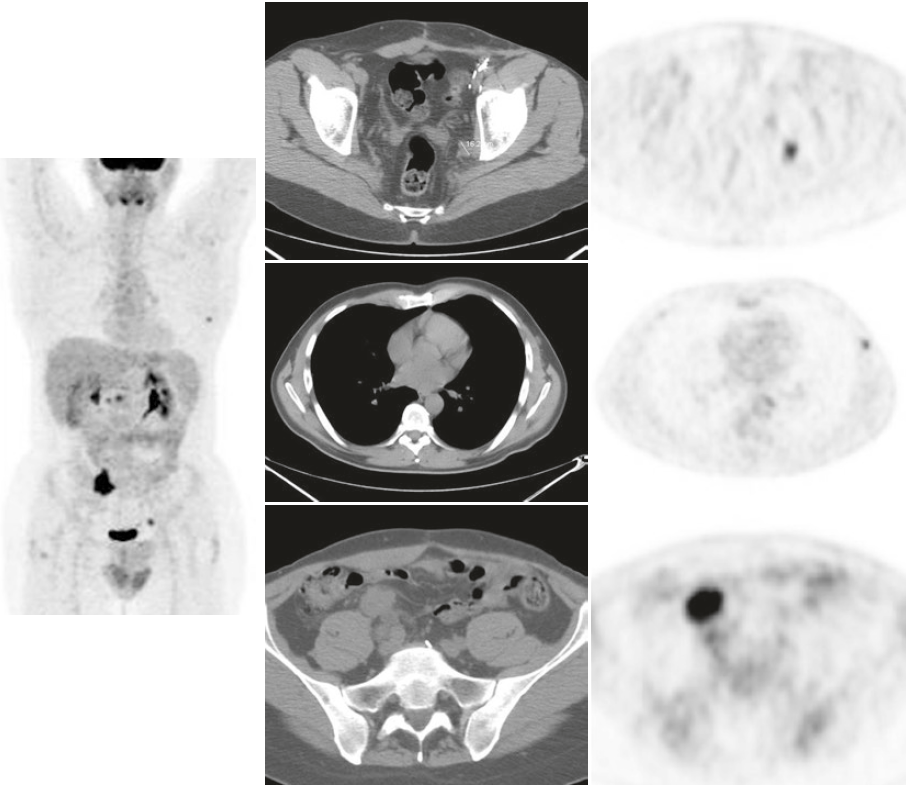

Ristadiazione di un melanoma vulvare avanzato.

La scansione PET/CT a corpo intero è fortemente suggerita negli stadi avanzati. In questo caso si hanno diverse aree di aumento dell’assorbimento a livello locale, nelle ossa, nei polmoni e nel fegato.

Sospetta ripresa addominale in paziente già operato per melanoma. Si osservano diverse aree ipermetaboliche nei linfonodi addominali e pelvici e nel torace sinistro (piccolo nodulo sottocutaneo).

La localizzazione dei siti di recidiva del melanoma può essere difficile e le immagini TC sono quasi necessarie per identificare correttamente le lesioni.